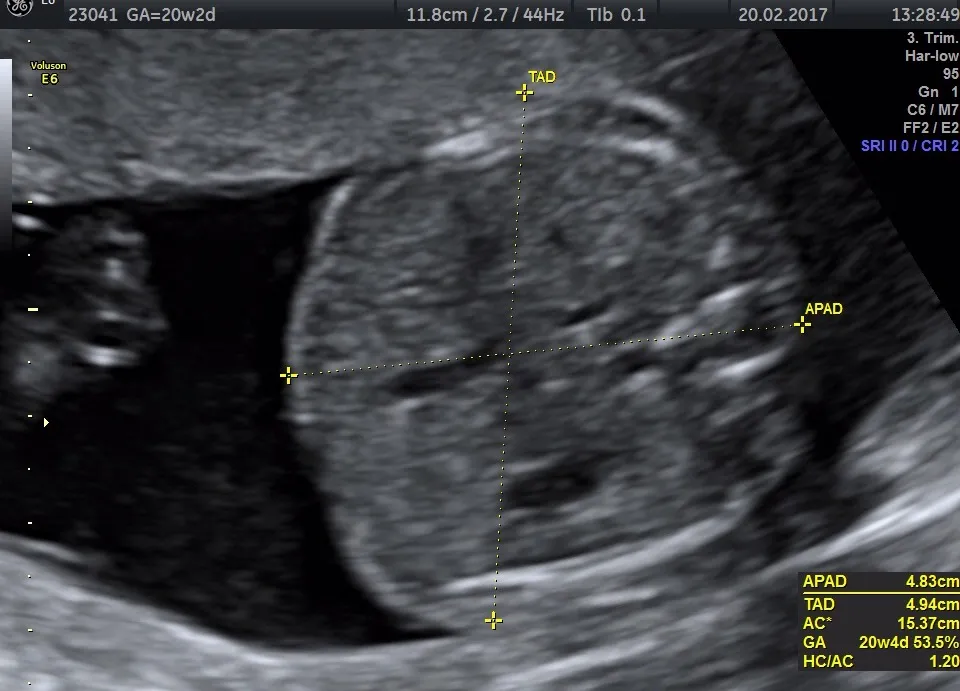

USG połówkowe, nazywane również genetycznym lub referencyjnym, to jedno z najważniejszych badań w całej ciąży. Wykonuje się je zazwyczaj między 18. a 22. tygodniem, a jego głównym celem jest niezwykle szczegółowa ocena anatomii płodu. Pozwala ono na wykluczenie lub wczesne wykrycie ewentualnych wad wrodzonych, co jest kluczowe dla dalszego postępowania medycznego i planowania opieki nad dzieckiem. To badanie daje nam ogromną wiedzę o zdrowiu maluszka.

Co dokładnie sprawdza lekarz podczas tego badania?

Podczas USG połówkowego lekarz skrupulatnie ocenia każdy element rozwijającego się organizmu dziecka:

- Mózg: Szczegółowa ocena struktury i rozwoju mózgu.

- Serce: Dokładna analiza budowy i pracy serca, w tym przepływów krwi przez wszystkie jego komory i naczynia.

- Nerki i żołądek: Sprawdzenie prawidłowego rozwoju i funkcjonowania tych kluczowych narządów.

- Kręgosłup: Ocena ciągłości i budowy kręgosłupa, aby wykluczyć wady takie jak rozszczep kręgosłupa.

- Kończyny: Sprawdzenie obecności i prawidłowego rozwoju wszystkich kończyn, dłoni i paluszków.

- Twarz: Ocena rysów twarzy i wykluczenie wad, np. rozszczepu wargi.